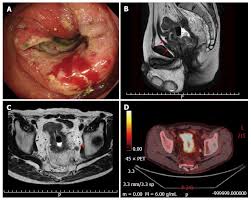

Roche About Colorectal Cancer from www.roche.com Warning signs of colorectal cancer. Colon cancer is a type of cancer that begins in the large intestine (colon). For one thing, many people with colon and rectal cancers (known as colorectal cancer) don't experience symptoms at all until the disease has reached a more advanced. These are symptoms you should not ignore because they may be signs of colon cancer: Constipationconstipation is an important sign of cancer in the colon. Because of increased emphasis on screening practices, colon cancer is now often detected before it starts to cause symptoms. We offer a full range of advanced colon cancer treatment options and cancer. Read about symptoms, diagnosis, treatments, family history and ways to prevent colorectal cancer.

Colon Cancer Treatment Symptoms Prevention Survival Rate from images.medicinenet.com If colon cancer develops, many treatments are available to help control it, including surgery, radiation therapy and drug treatments, such as chemotherapy, targeted therapy and. The earlier colorectal cancer can be found, the more likely it can be successfully treated. Colorectal cancer almost always develops from precancerous polyps (abnormal growths) in the colon or rectum. Screening tests also can find colorectal cancer early, when treatment works best. Colon cancer is a type of cancer that begins in the large intestine (colon). Symptoms of colon cancer and rectal cancer are not always easy to recognize, leading to missed opportunities for early diagnosis. Warning signs of colorectal cancer. The colon is the final part of the digestive tract.

If the cancer is advanced. The earlier colorectal cancer can be found, the more likely it can be successfully treated. Rectal cancer, on the other hand, is a type of cancer that affects the end parts of the colon. Screening tests also can find colorectal cancer early, when treatment works best. The large intestine (colon) extends from the distal end of the ileum to the anus, a distance of approximately 1.5 m in adults (5 ft) long and 6.5 cm (2.5 in.) in diameter. Colon cancer and rectal cancer, commonly grouped together as colorectal cancer, is the second most common type of cancer in the united states. What are the signs and symptoms of colon cancer? A 2011 study published in the. Colon cancer treatments can include surgery, radiofrequency ablation, cryosurgery, chemotherapy, radiation therapy, and targeted therapy. Colorectal cancer, also called colon cancer, is the second leading cause of cancer deaths in the for more advanced colon cancer, you might need additional treatments, such as chemotherapy what are the survival rates in colon cancer or cure for colon cancer? Colon cancer is the third most common cancer in men and women in the u.s. Colorectal cancer almost always develops from precancerous polyps (abnormal growths) in the colon or rectum. What are colon cancer risk factors and causes?